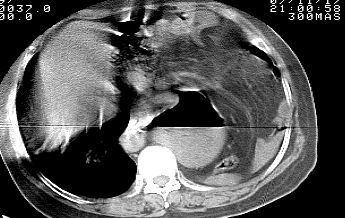

标题: CT10753:女, 64岁 隔疝 [打印本页]

标题: CT10753:女, 64岁 隔疝

女, 64岁 三十年前胸部外伤史, 间断胸闷,

典型左侧膈疝,疝出物为胃和大网膜,纵隔右移

同意左侧膈疝,不过,有过外伤史,左肺有受压征象,同时有胸膜增厚。

左侧隔疝(创伤性?),与外伤关系大。